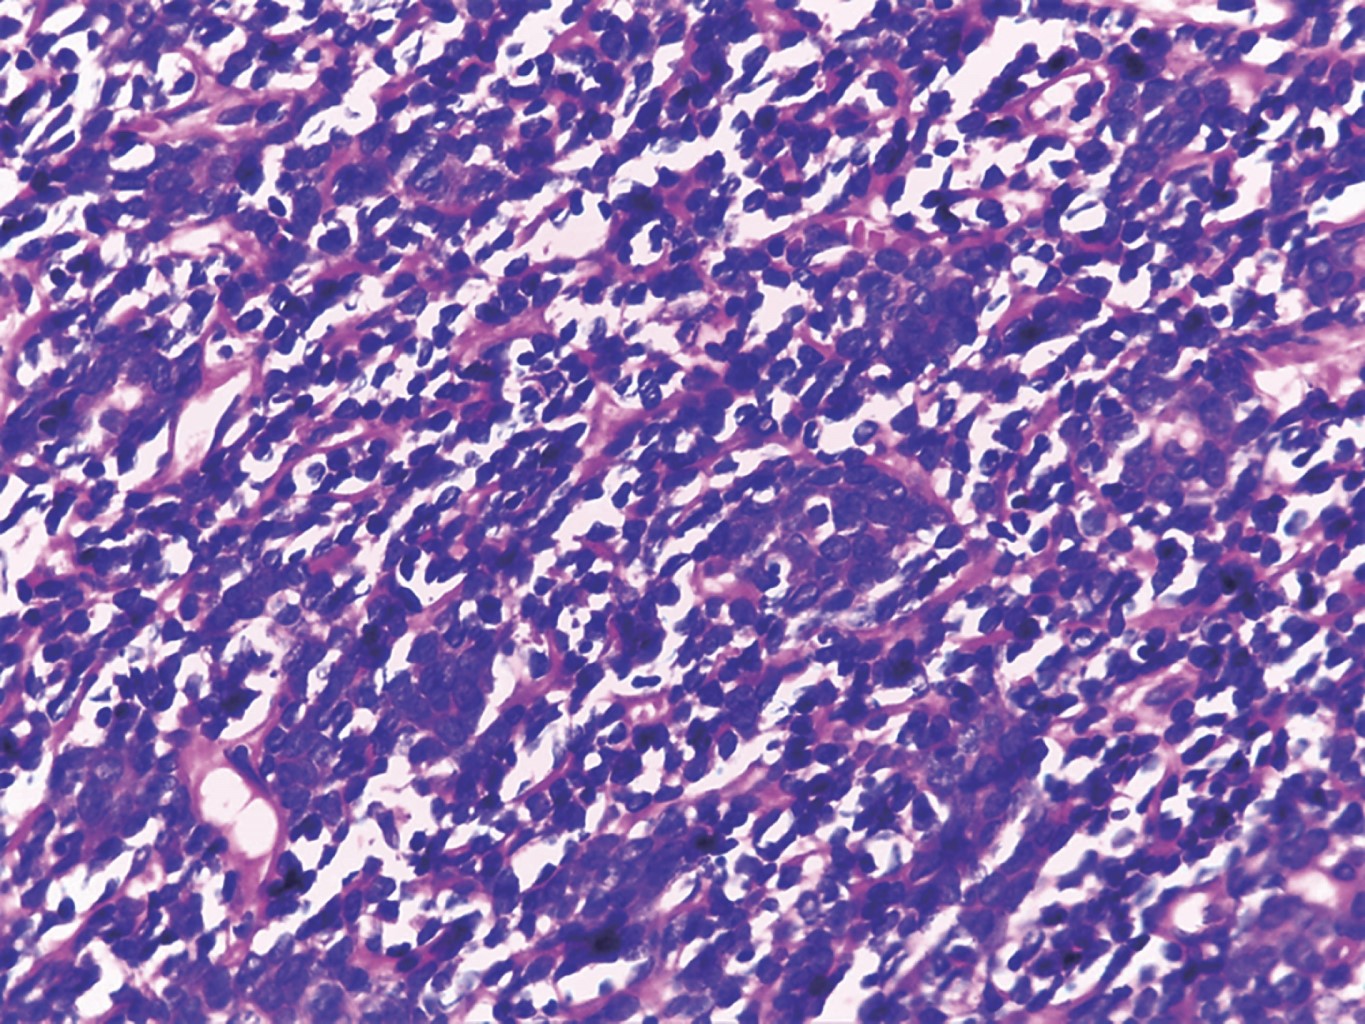

Figure 3